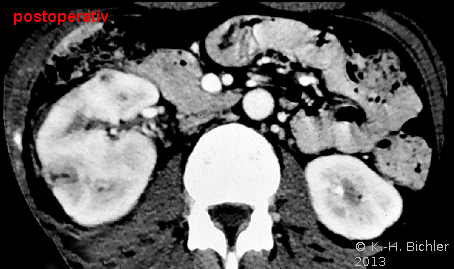

Beispielhaft die Darstellung eines ausgedehnten Nierenabszesses in Sonographie, CT und AUR (Abbildung 6).

Die Nierenfreilegung und Abszessdrainage bzw. der postoperative Krankheitsverlauf im obigen Fall (s. Abbildung 6) sind in den Abbildungen dargestellt (Abbildung 9,10).